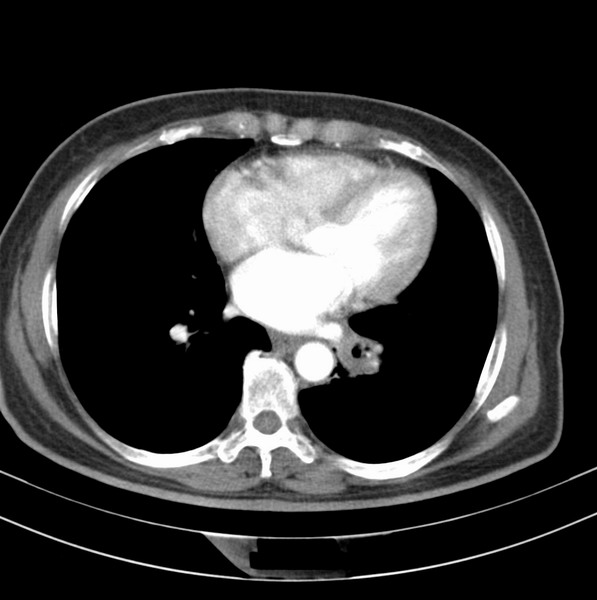

女、63

咳嗽、胸痛四个月

考虑左下肺中央型肺癌

支持左下中央型肺癌伴阻塞性炎症不张。

包绕左下肺基底段的不规则的软组织肿块,段支气管腔变形、狭窄及阻塞性炎症,病变区不规则强化,又是老年女性支持楼上看法。

考虑左肺下叶中央型肺癌伴阻塞性肺炎、支气管黏液嵌塞。

典型病例:左下肺基底段中央型肺癌,相应支气管狭窄并阻塞性炎症